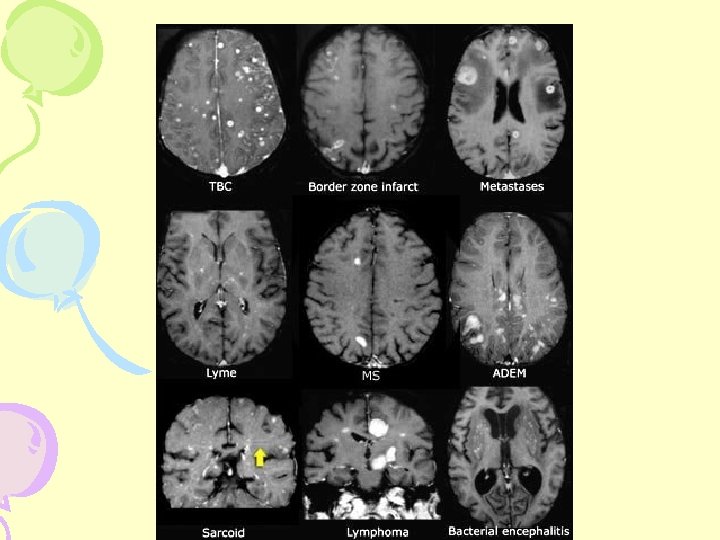

Differential Diagnosis • • Encephalomyelitis CNS Vasculitis Lyme Disease Lupus Erythematosus Spastic Paraparesis Behçet Syndrome Vitamin B-12 Deficiency and Syphilis Hereditary Degenerative Disorders